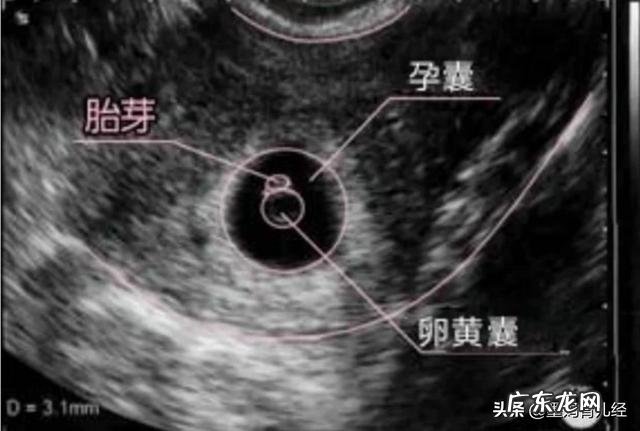

2.超声检查

超声检查是检查早孕和确定胎儿大小最快速、准确的方法,最早可在孕5周的时候作出早孕诊断,超声检查也分阴超和腹部b超,阴超比腹超可提前5-7日确诊早孕 。

停经35日时,宫腔内就可见圆形或椭圆形妊娠囊,妊娠6周时就可见到胚芽和原始心管搏动,早期的超声检查还可确定宫内妊娠是否存活以及排除异位妊娠、估算孕周等……